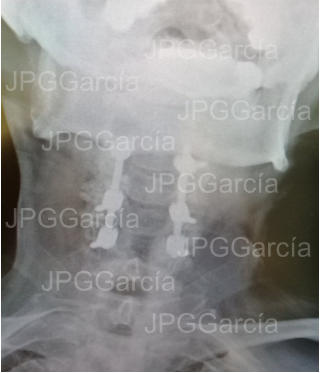

Instrumentación Cervical Posterior con tornillos y barras por Conducto Cervical Estrecho (vistas lateral y anteroposterior)

Radiografía lateral de cuello post quirúrgica la cual muestra la instrumentación cervical posterior colocada y una laminectomía cervical amplia para liberación del tejido medular